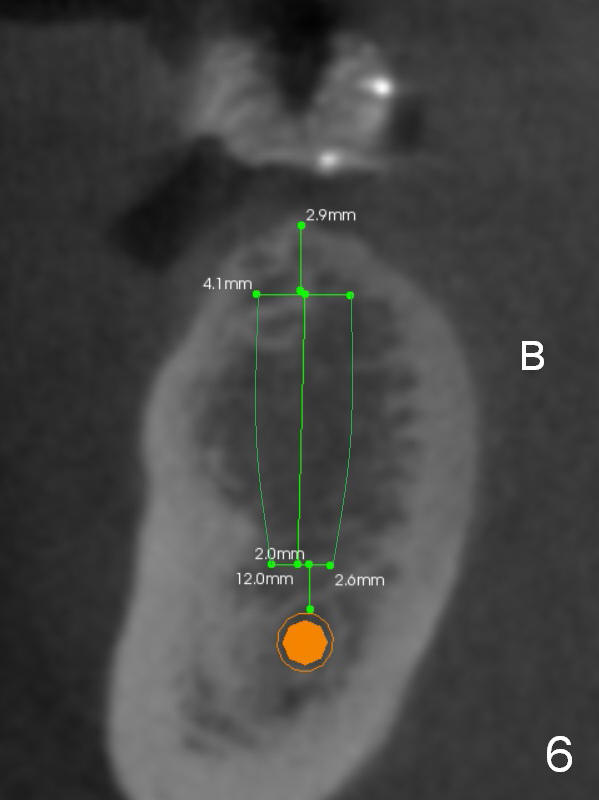

The first implant will be placed at #29 (Fig.4,5). The pointed ridge will be flattened to start osteotomy (Fig.6,7 (surgical handpiece)). The buccolingual dimension of the flattened ridge should be ~ 6 mm. The initial depth will be 12 mm. Take the 1st PA. A restorative high speed handpiece may be needed to remove the enamel of the mesial surface of #30 and the distal surface of #28 to increase space for implant placement.